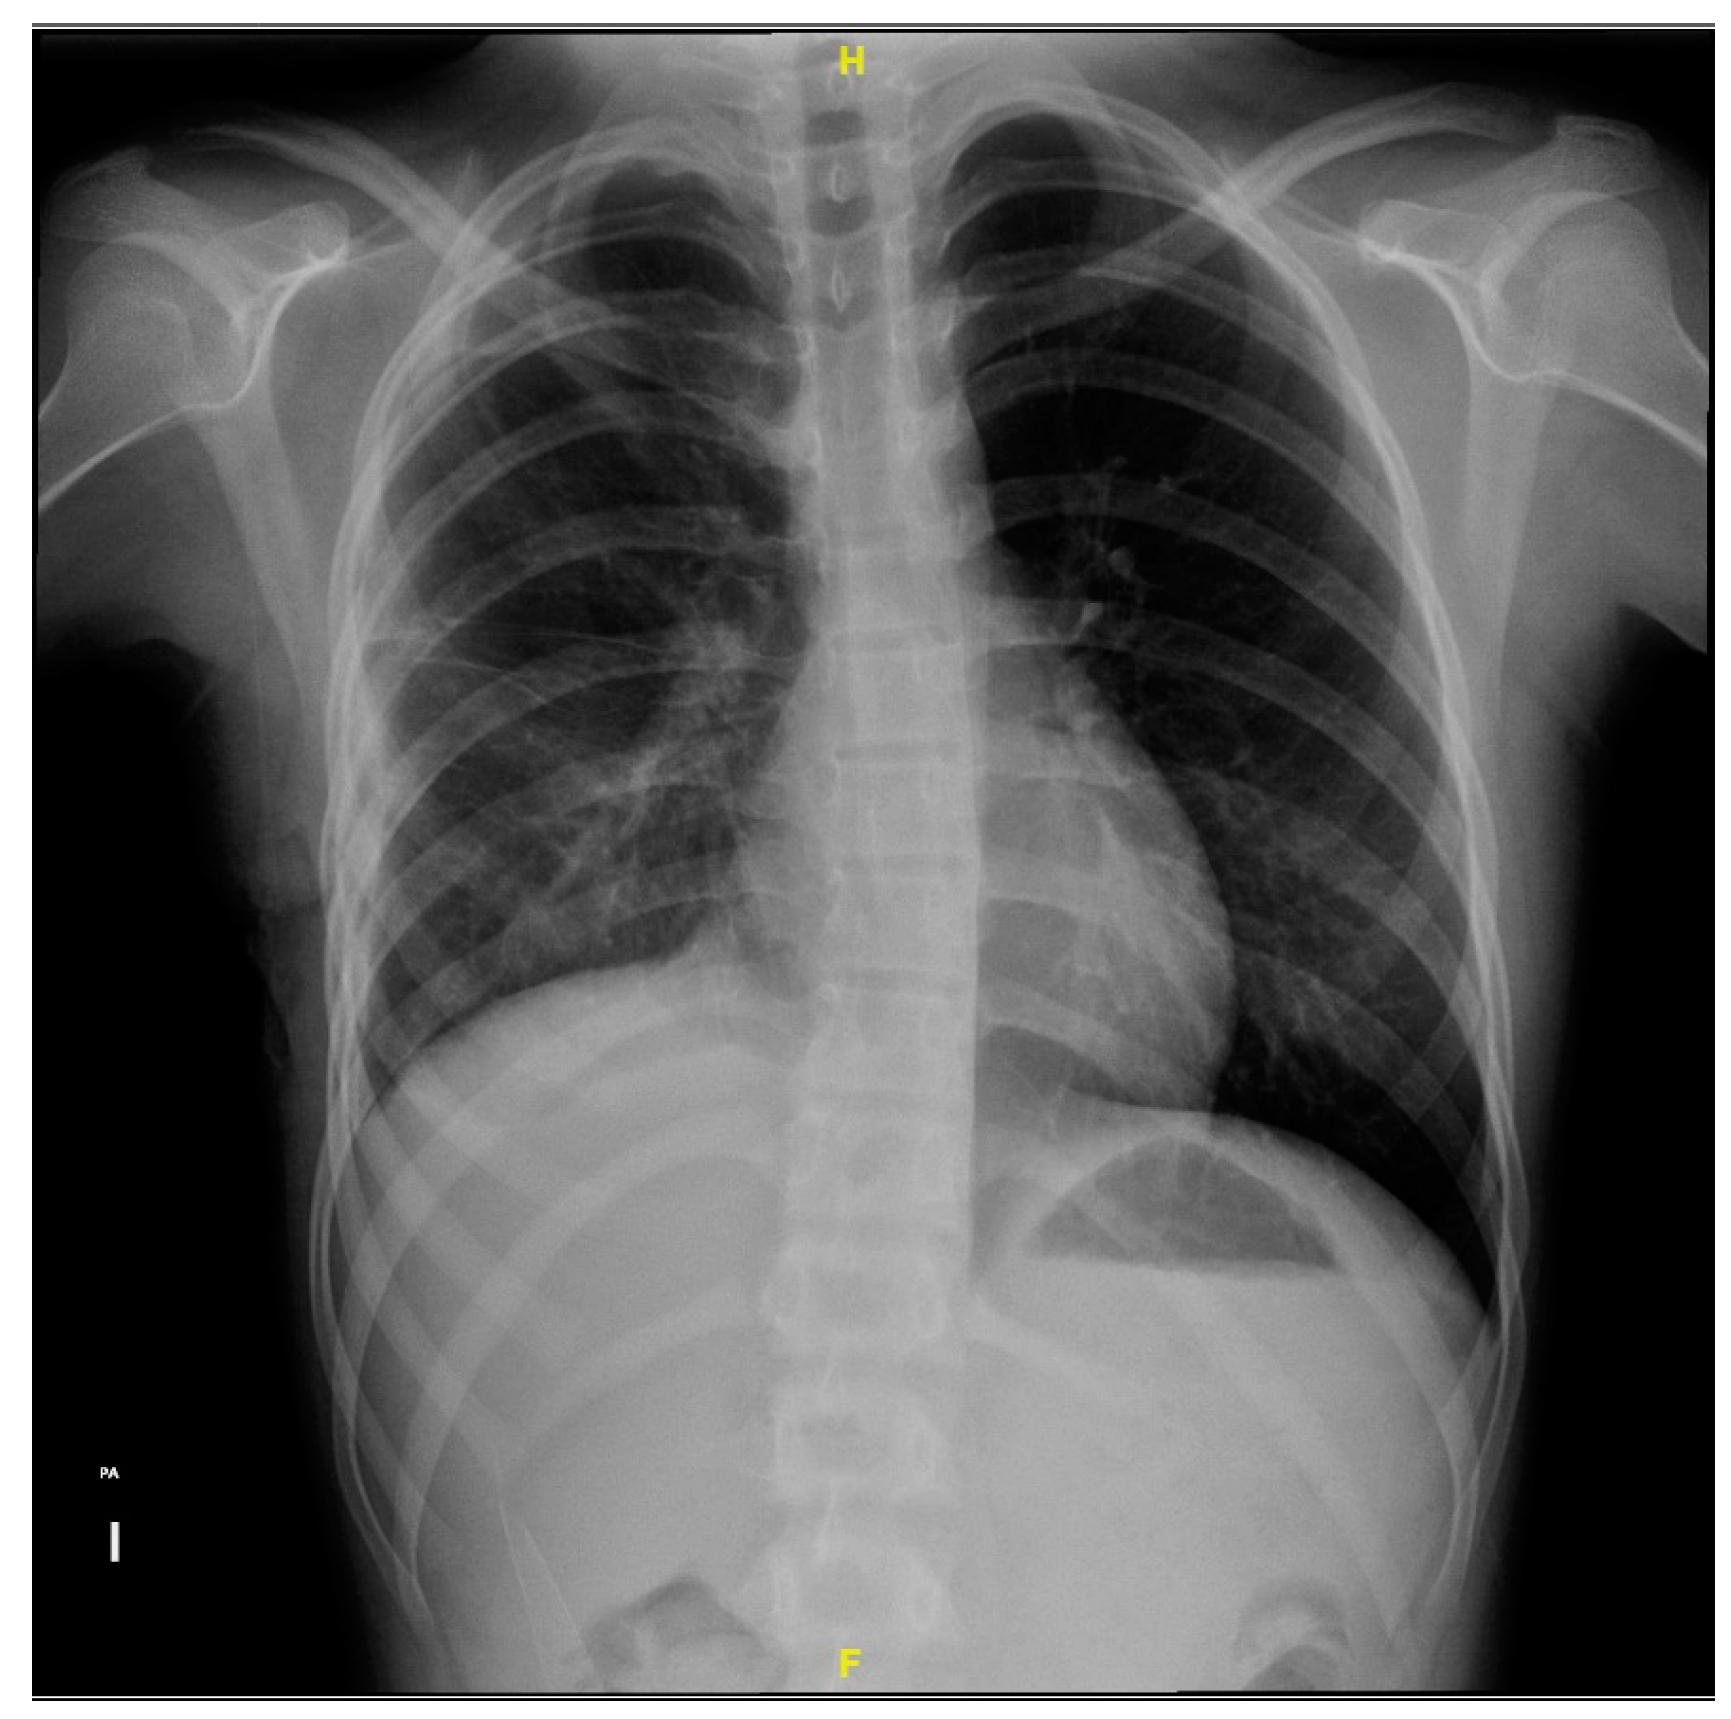

2. Case Presentation